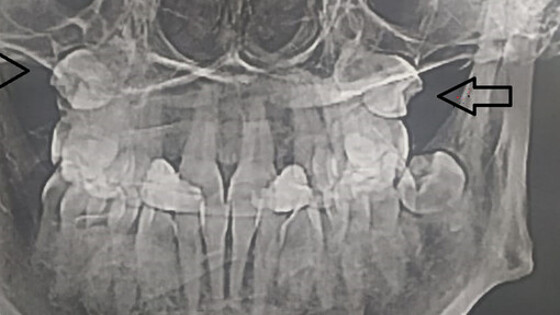

Жительница Самары обнаружила, что в гайморовых пазухах у нее выросли зубы, сообщает ГТРК "Самара".

Об этом женщина узнала, сделав МРТ.

Выяснилось, что "четверки" (зубы которые идут после клыков) выросли вместо челюсти в носу. Жительницу Самары направили на операцию, где под общим наркозом удалили зубы.